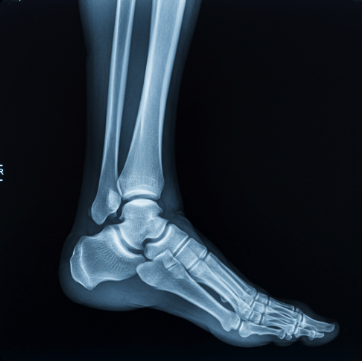

복숭아뼈는 발목 안쪽과 바깥쪽에 튀어나온 뼈로, 정식 명칭은 '복사뼈'입니다.

▫️ 골절 및 타박상 - 직접적인 충격으로 인한 손상

보조기 착용 - 심한 염좌나 골절의 경우 깁스나 부목으로 고정합니다.

수술적 치료 - 인대가 완전히 파열되었거나 골절이 심한 경우 수술이 필요할 수 있습니다.